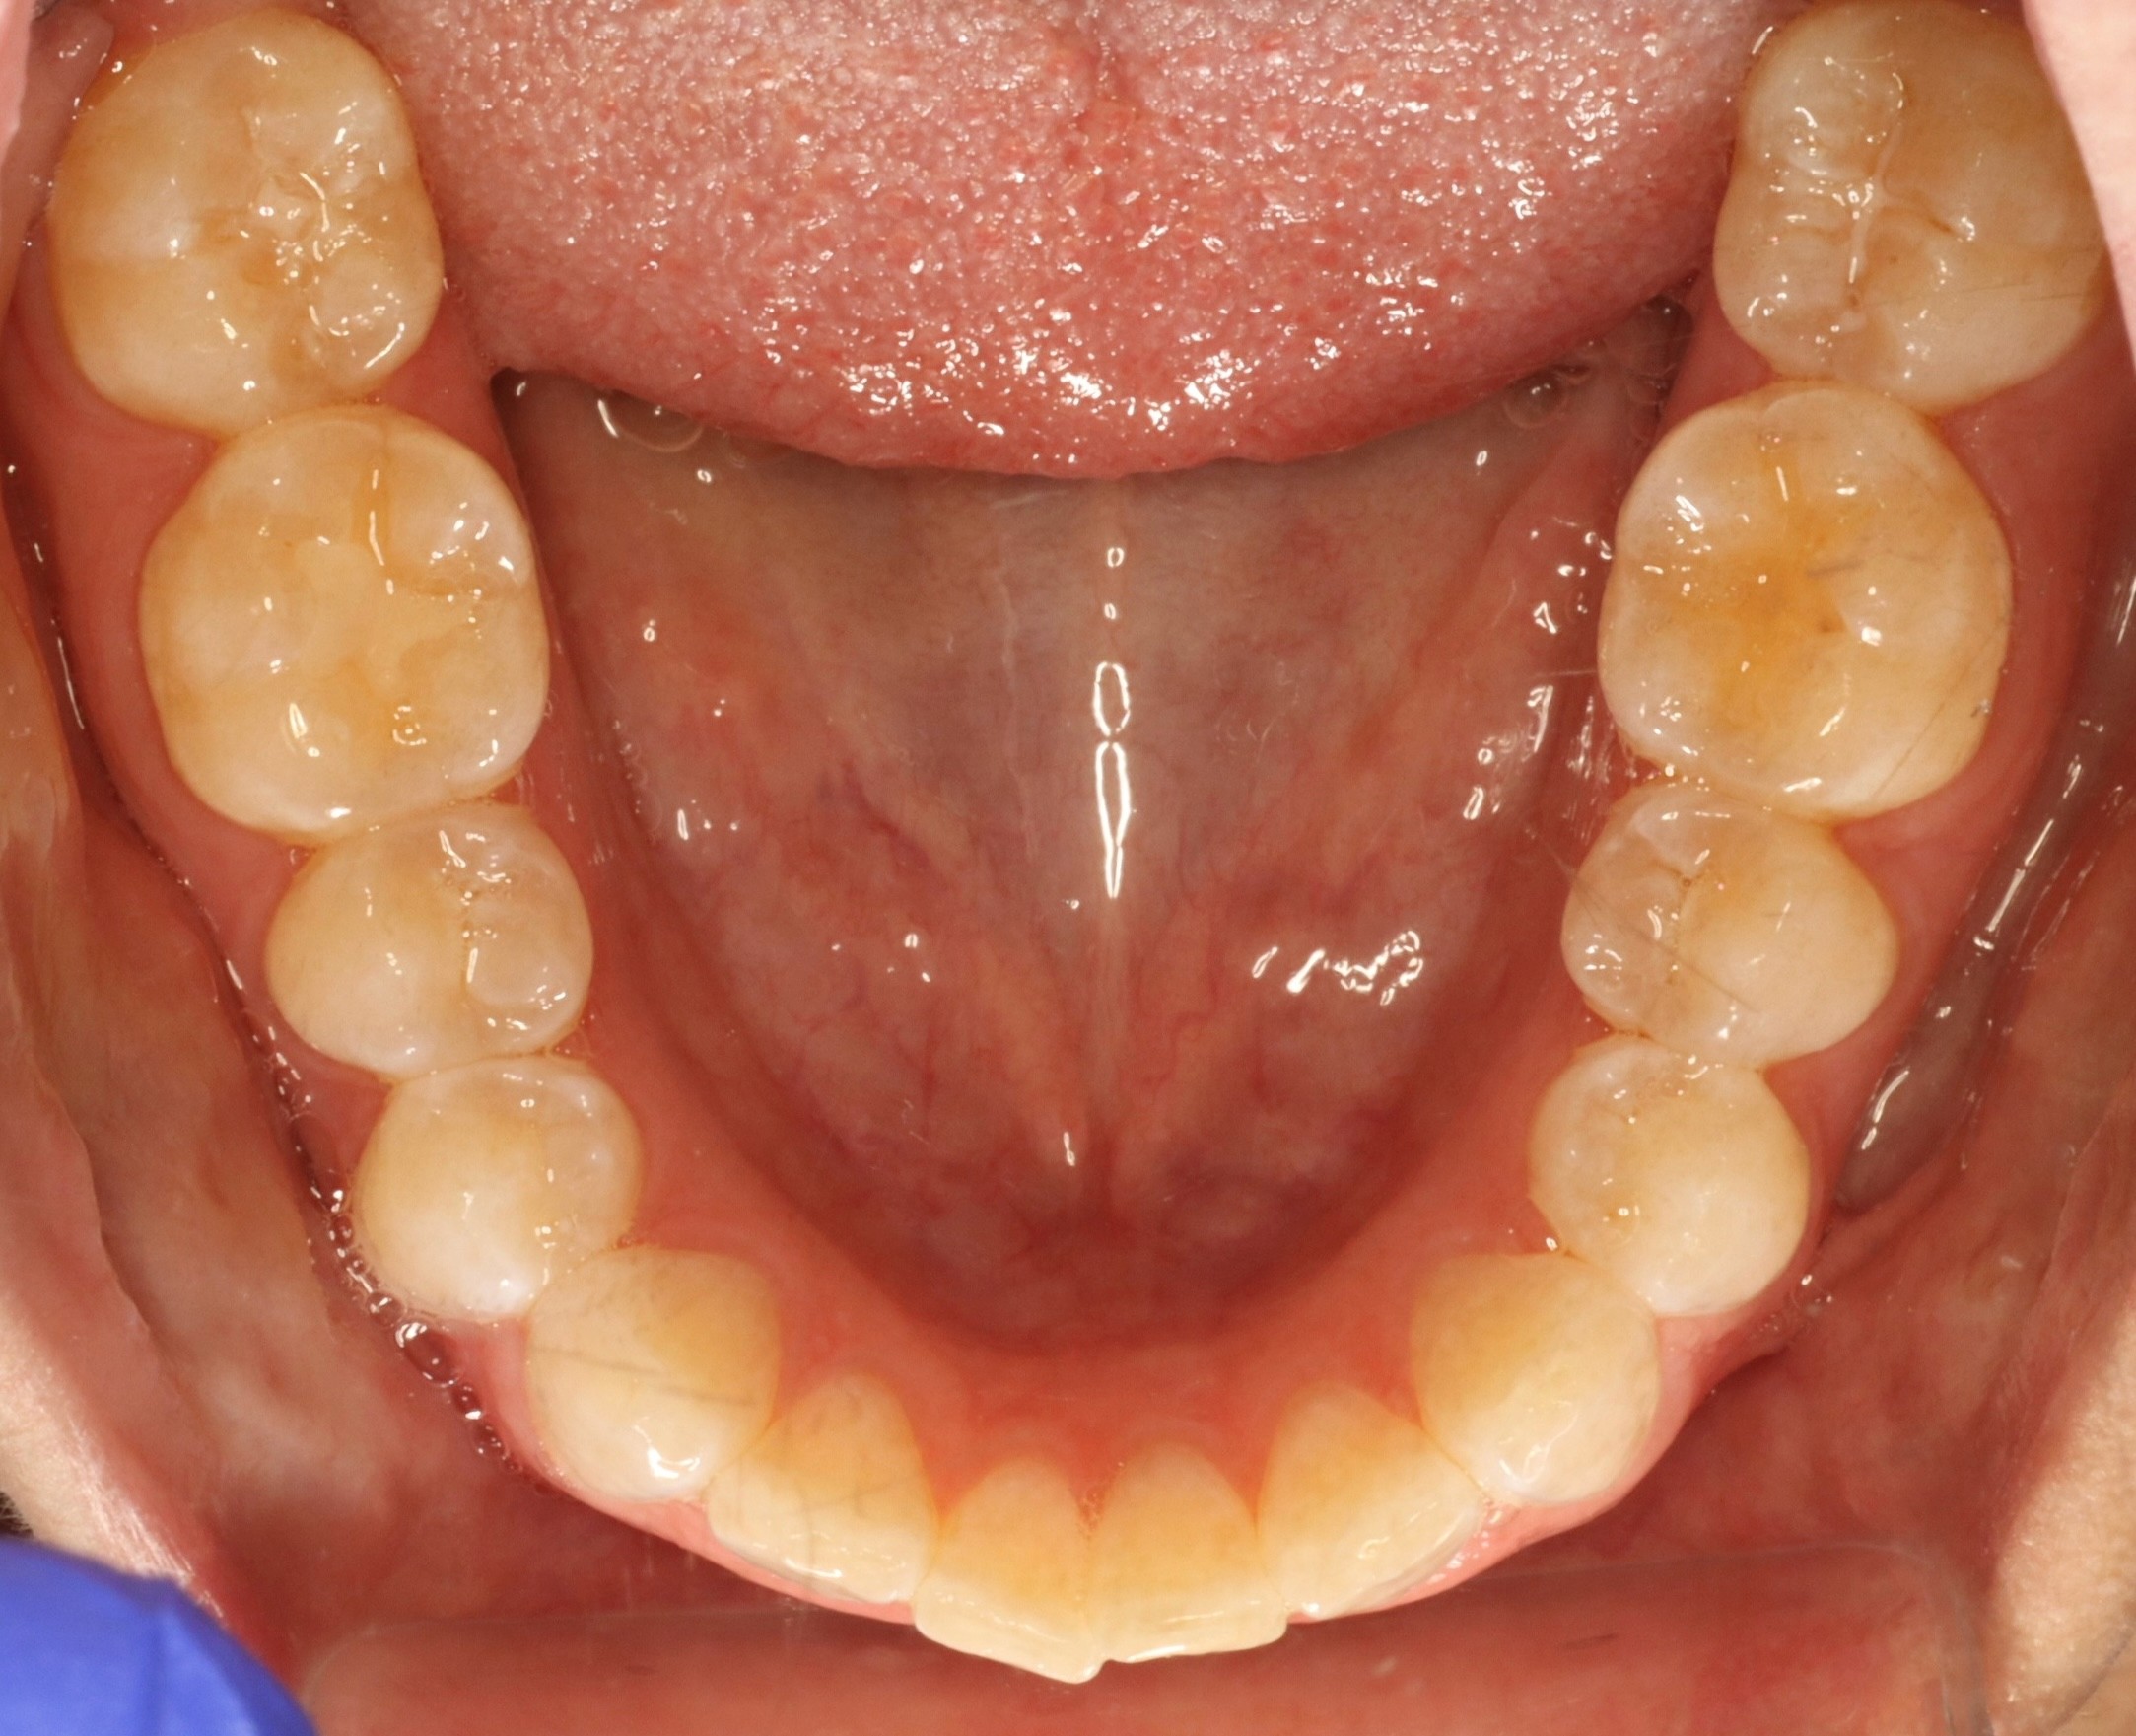

Diagnosis: Deep bite, lower anterior crowding, rotated upper lateral, arch misalignment, wear on teeth from grinding

Initial treatment

INTRAORAL